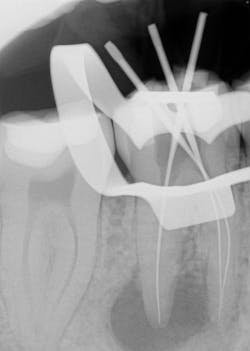

Various clinical presentations and risk factors can influence endodontic success or failure, including but not limited to the quality of the root canal performed and the seal of the coronal restoration.2 In addition to the aforementioned factors, the presence and size of a periapical lesion can directly affect the prognosis and treatment outcome. Classic literature highlights this shift in long-term success rates from 96% for vital/nonvital cases without the presence of a periapical lesion to 86% when a periapical lesion is present.3

Periapical radiographs have been commonly used to evaluate the size of periapical lesions. However, periapical radiographs have limitations, because the information is rendered in only two dimensions. A periapical lesion can only be detected in the radiograph when the mineral loss of bone reaches 30%–50%.4